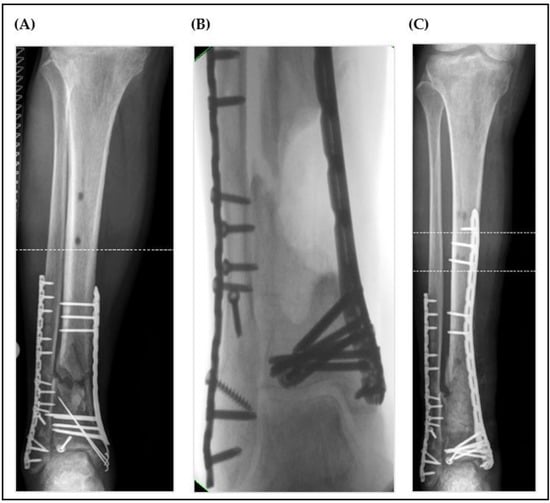

1. Introduction

2. Material and Methods

2.3. Surgical Technique